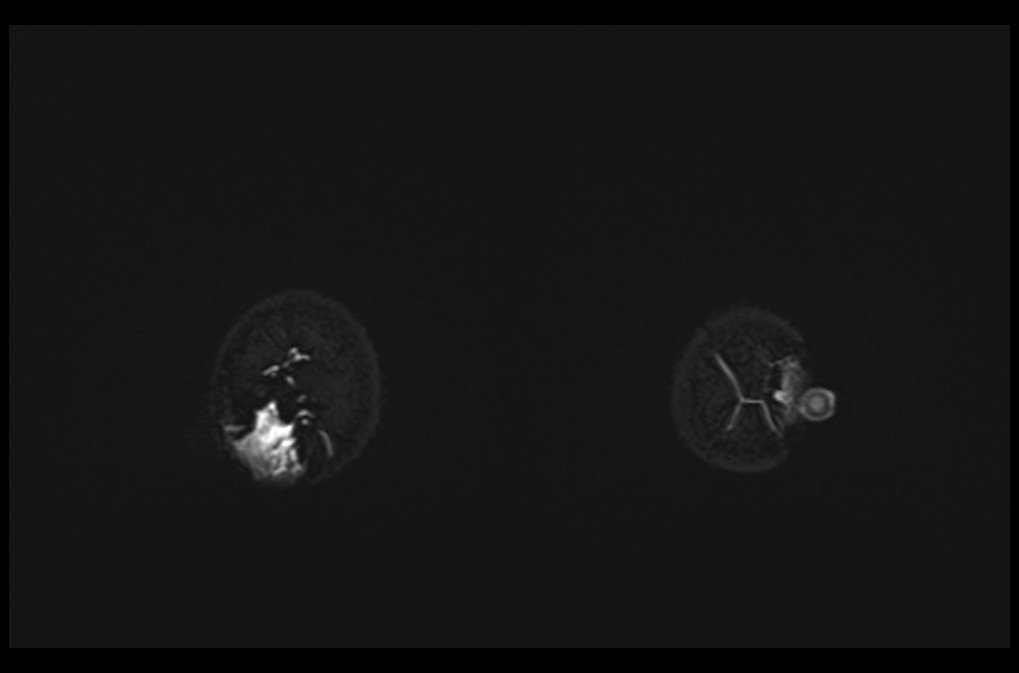

MRI breast implant stir coronal images 2 - MRI